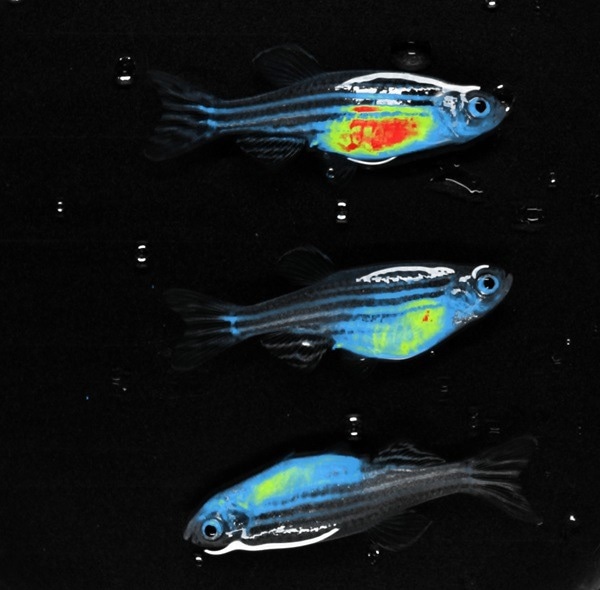

RED FLI - Zebrafish. Image Credit: Scintica Instrumentation Inc